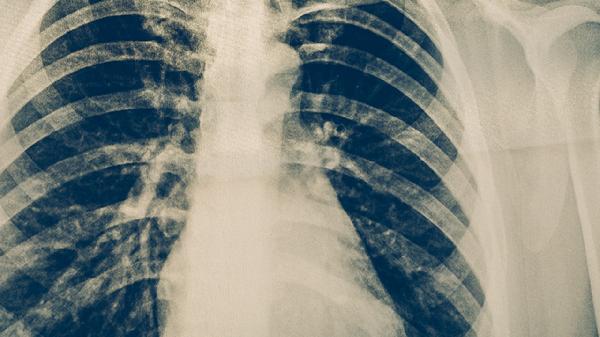

初期感染肺结核征兆

肺结核初期感染征兆主要包括咳嗽、低热、盗汗、乏力、体重下降等。肺结核是一种由结核分枝杆菌引起的慢性传染病,早期症状较为隐匿,容易被忽视。

咳嗽是肺结核最常见的早期症状,通常表现为持续性干咳或伴有少量痰液。随着病情进展,咳嗽可能加重并伴有血痰。若咳嗽持续超过两周且无明显缓解,需警惕肺结核的可能性。

肺结核初期症状较为隐匿,容易被忽视。若出现持续性咳嗽、低热、盗汗、乏力、体重下降等症状,建议及时就医进行相关检查。日常生活中,注意保持良好的卫生习惯,避免与肺结核患者密切接触,增强免疫力,合理饮食,适当运动,有助于预防肺结核的发生。